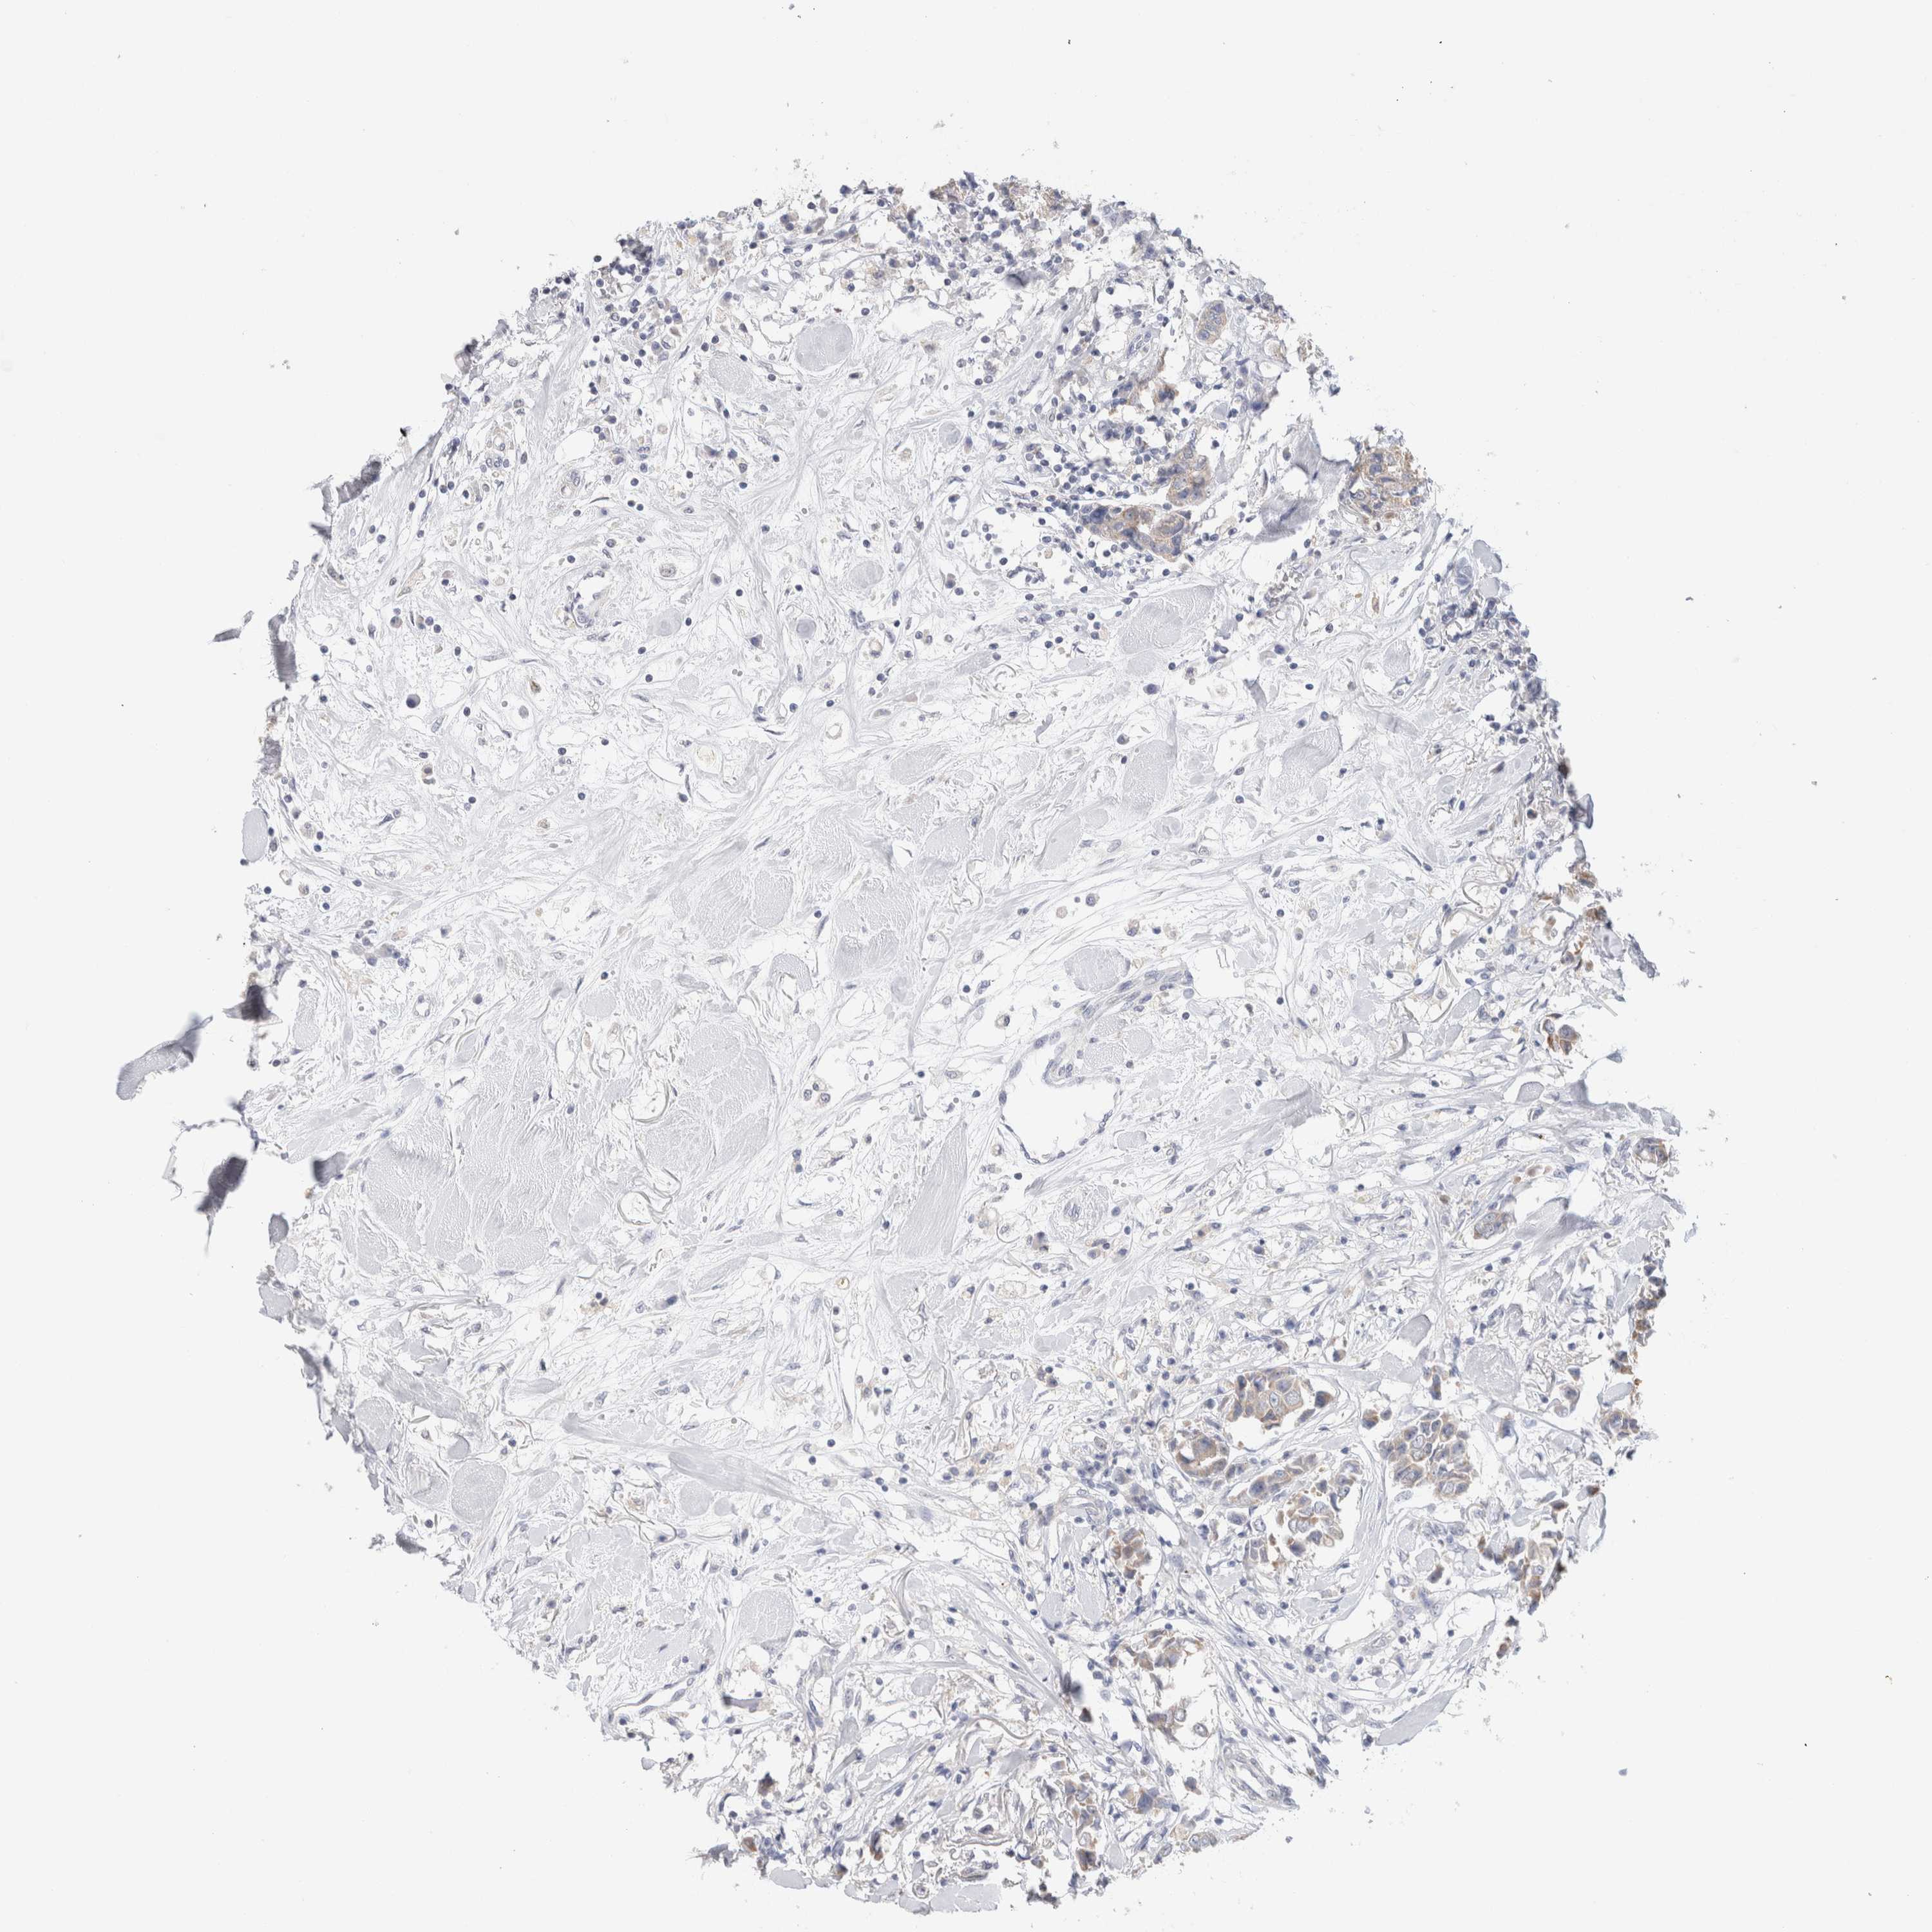

CANCER BREAST CANCER Show tissue menu

BRCA TCGA BRCA VALIDATION PROTEIN EXPRESSION